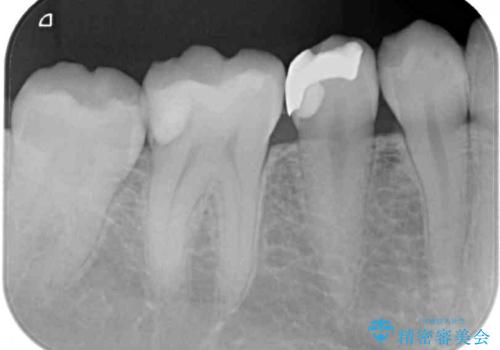

レントゲン写真などから、速やかに処置を行うべき歯が2歯あったため、それぞれセラミックインレーとPGAインレー(ゴールドインレー)にて修復治療を行うこととしました。